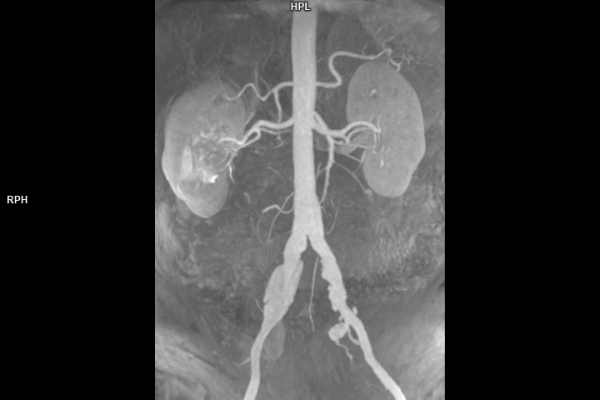

• Gefäßdiagnostik (CT-Angiographie)

Wir bieten ein breites Spektrum an Untersuchungen an, von Standarduntersuchungen der Gelenke, Organe oder großflächigen Körperregionen bis zu Spezialuntersuchungen zum Beispiel des Herzen oder der Gefäße. Zusätzlich werden Angiographien (Darstellung von Blutgefäßen), Endometriose-Abklärungen und Mamma-Untersuchungen durchgeführt. Genauere Details können Sie der MRT/CT-Übersicht und der Preisliste entnehmen, oder Sie wenden sich direkt an unser Team, das Sie gerne zur passenden Untersuchung berät.

• Gefäßdiagnostik